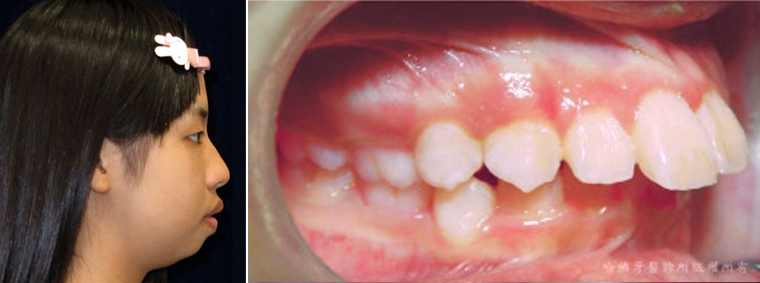

在台灣有許多的「齒顎不整」存在著「下顎骨發育不足」的症候。當患者存在「下顎骨發育不足」症候時,由於下顎骨過度內縮,會令下顎門齒也極度內縮,而促使下顎門齒與上顎門齒呈現過大距離。 這個門齒間過大距離令上顎門齒顯得更加明顯往前傾斜,也令嘴唇閉合困難(圖18)。

(圖18)在台灣有許多的「齒顎不整」存在著「下顎骨發育不足」的症候。當患者存在「下顎骨發育不足」症候時,由於下顎骨過度內縮,會令下顎門齒也極度內縮,而促使下顎門齒與上顎門齒呈現過大距離。 這個門齒間過大距離令上顎門齒顯得更加明顯往前傾斜,也令嘴唇閉合困難。